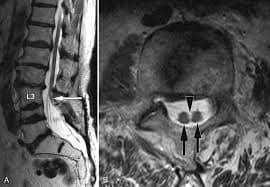

فقد تم اجراء عمليه جراحيه معقدة ونادره لطفل يبلغ من العمراسبوعين يعاني من تشوه خلقي مزدوج من فتق سُحائي وتشوه في العمود الفقري مع وجود نتوء عظمي يتسبب بـ نخاع شوكي منشق (مزدوج (

ولأول مرة في مستشفى الزرقاء الحكومي من قبل الدكتور فراس حداد / استشاري أول جراحة الدماغ والأعصاب، رئيس إختصاص جراحة الدماغ والأعصاب في الخدمات الطبية الملكية سابقاً الذي قام بإجراء العمليه، بمساعدة نخبة مميزة من الكادر الطبي على رأسهم الدكتور رأفت بواعبه مقيم جراحه الدماغ والاعصاب. كما شارك الكادر التمريضي وانجاح العملية وعلى راسهم الممرض مراد الزيود و الممرضة هبه المومني و الممرضة خوله ابوهاني جهودكم مشكوره بالاضافة الى أطباء قسم التخدير اطباء التخدير الدكتور أنس وفنية التخدير إيناس